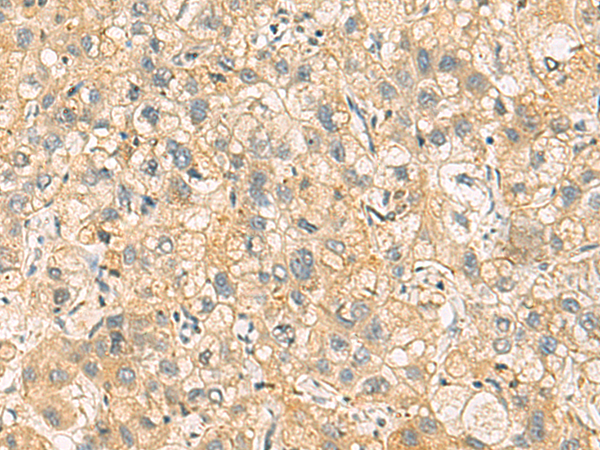

分类: 科研抗体货号: P10330别名: EAPF; PHAFIN2; ZFYVE18应用: WB,IHC反应种属: Human, Mouse